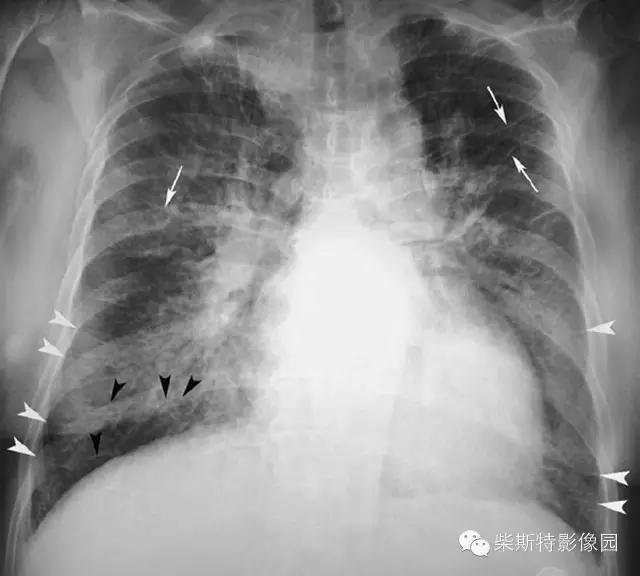

经典图像第一例:

小编标注:蓝色线是克氏A线,红色线是克氏B线,黄色网格状线是克氏C线。

1.A线:表现为直的或近乎直的指向肺门的不分支的致密细线影,呈水平走行,长度约2~4cm,但很少超过4cm,宽度为0.5~1mm。多见于上肺野。

2.B线:为克氏线征中最常见者,表现为较短的不分又的梯状致密横线影,长不超过2cm,宽不超过1mm。常位于两下肺野的外带(肋隔角)平行的次出现,亦可见于中肺野,但从不出现于上肺野。其外端常抵达胸膜缘并与之垂直,以右侧为多见.

3.C线:少见,表现为很细很短的线状影,可向任何方向走行,相互交织呈蛛网状影。其可见于肺的任何部分,好发于下肺。